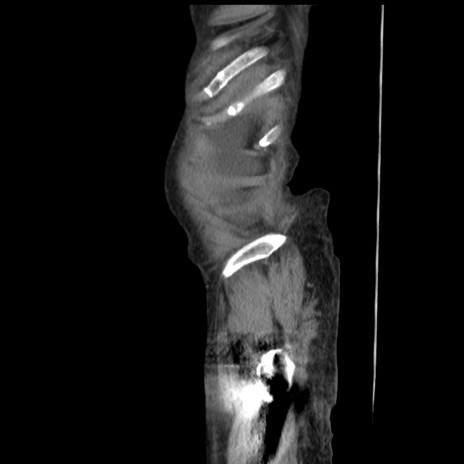

症例31(矢状断像)

【症例】80歳代 女性

【主訴】腹部膨満感

【現病歴】他院にて肝硬変にてフォロー中。1週間前から便秘、腹部膨満感、臍部腫瘤あり受診となる。

【既往歴】肝硬変

【身体所見】腹部膨隆あり、皮膚変化なし、疼痛なし。

【データ】WBC 4600、CRP 0.25